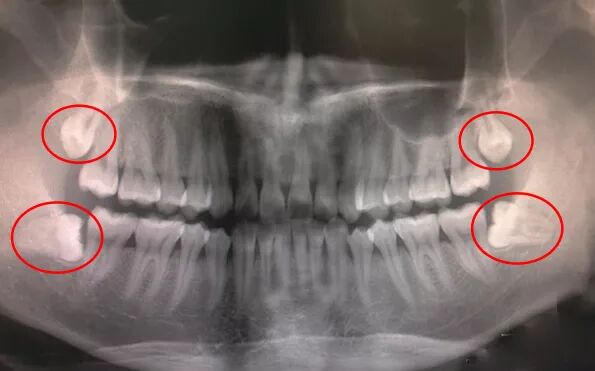

智齿是指人类口腔内牙槽骨上最里面的第三颗磨牙,从正中的门牙往里数刚好是第八颗牙齿。由于它萌出时间很晚,一般在16~25岁间萌出,此时人的生理、心理发育都接近成熟,被当做“智慧到来”的象征,因此俗称为“智齿”。

智齿在生长方面,个体有很大差异,通常情况下应该有上下左右对称的4颗牙,有的人少于4颗甚至没有,极少数人会多于4颗。具体长出来的年龄差异也很大,有的人会在20岁之前长出,有人40、50岁才长或者终生不长,这都是正常现象。

1、阻生智齿

阻生齿是指因为生长的位置不当,导致不能萌出到正常咬合位置的牙齿。因此阻生智齿,通俗点来说,就是“阻碍生长的智齿”,是指因为软组织问题或颌骨骨量不足,智齿不能正常萌出,被牙龈或牙槽骨包裹在里面,经常引发炎症、疼痛。

一般我们说牙疼拔智齿,很多就是阻生智齿,因为大部分甚至全部都埋伏在颌骨中,拔除的难度也比较大,需要削掉一部分颌骨,再将智齿切碎取出,如下图: